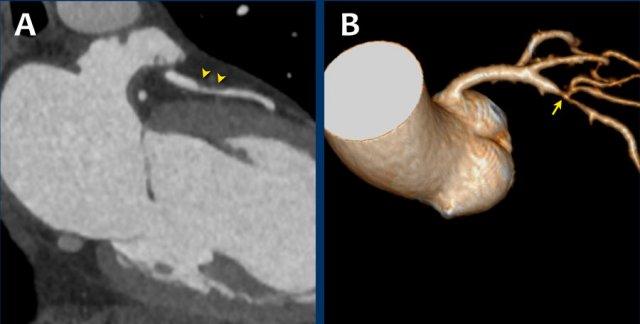

This image is of a patient with Kawasaki disease.

There is a coronary artery aneurysms (8 mm and 6 mm diameter)

of the LAD.

Please also note the presence of

partially calcified plaque in the proximal aneurysm.